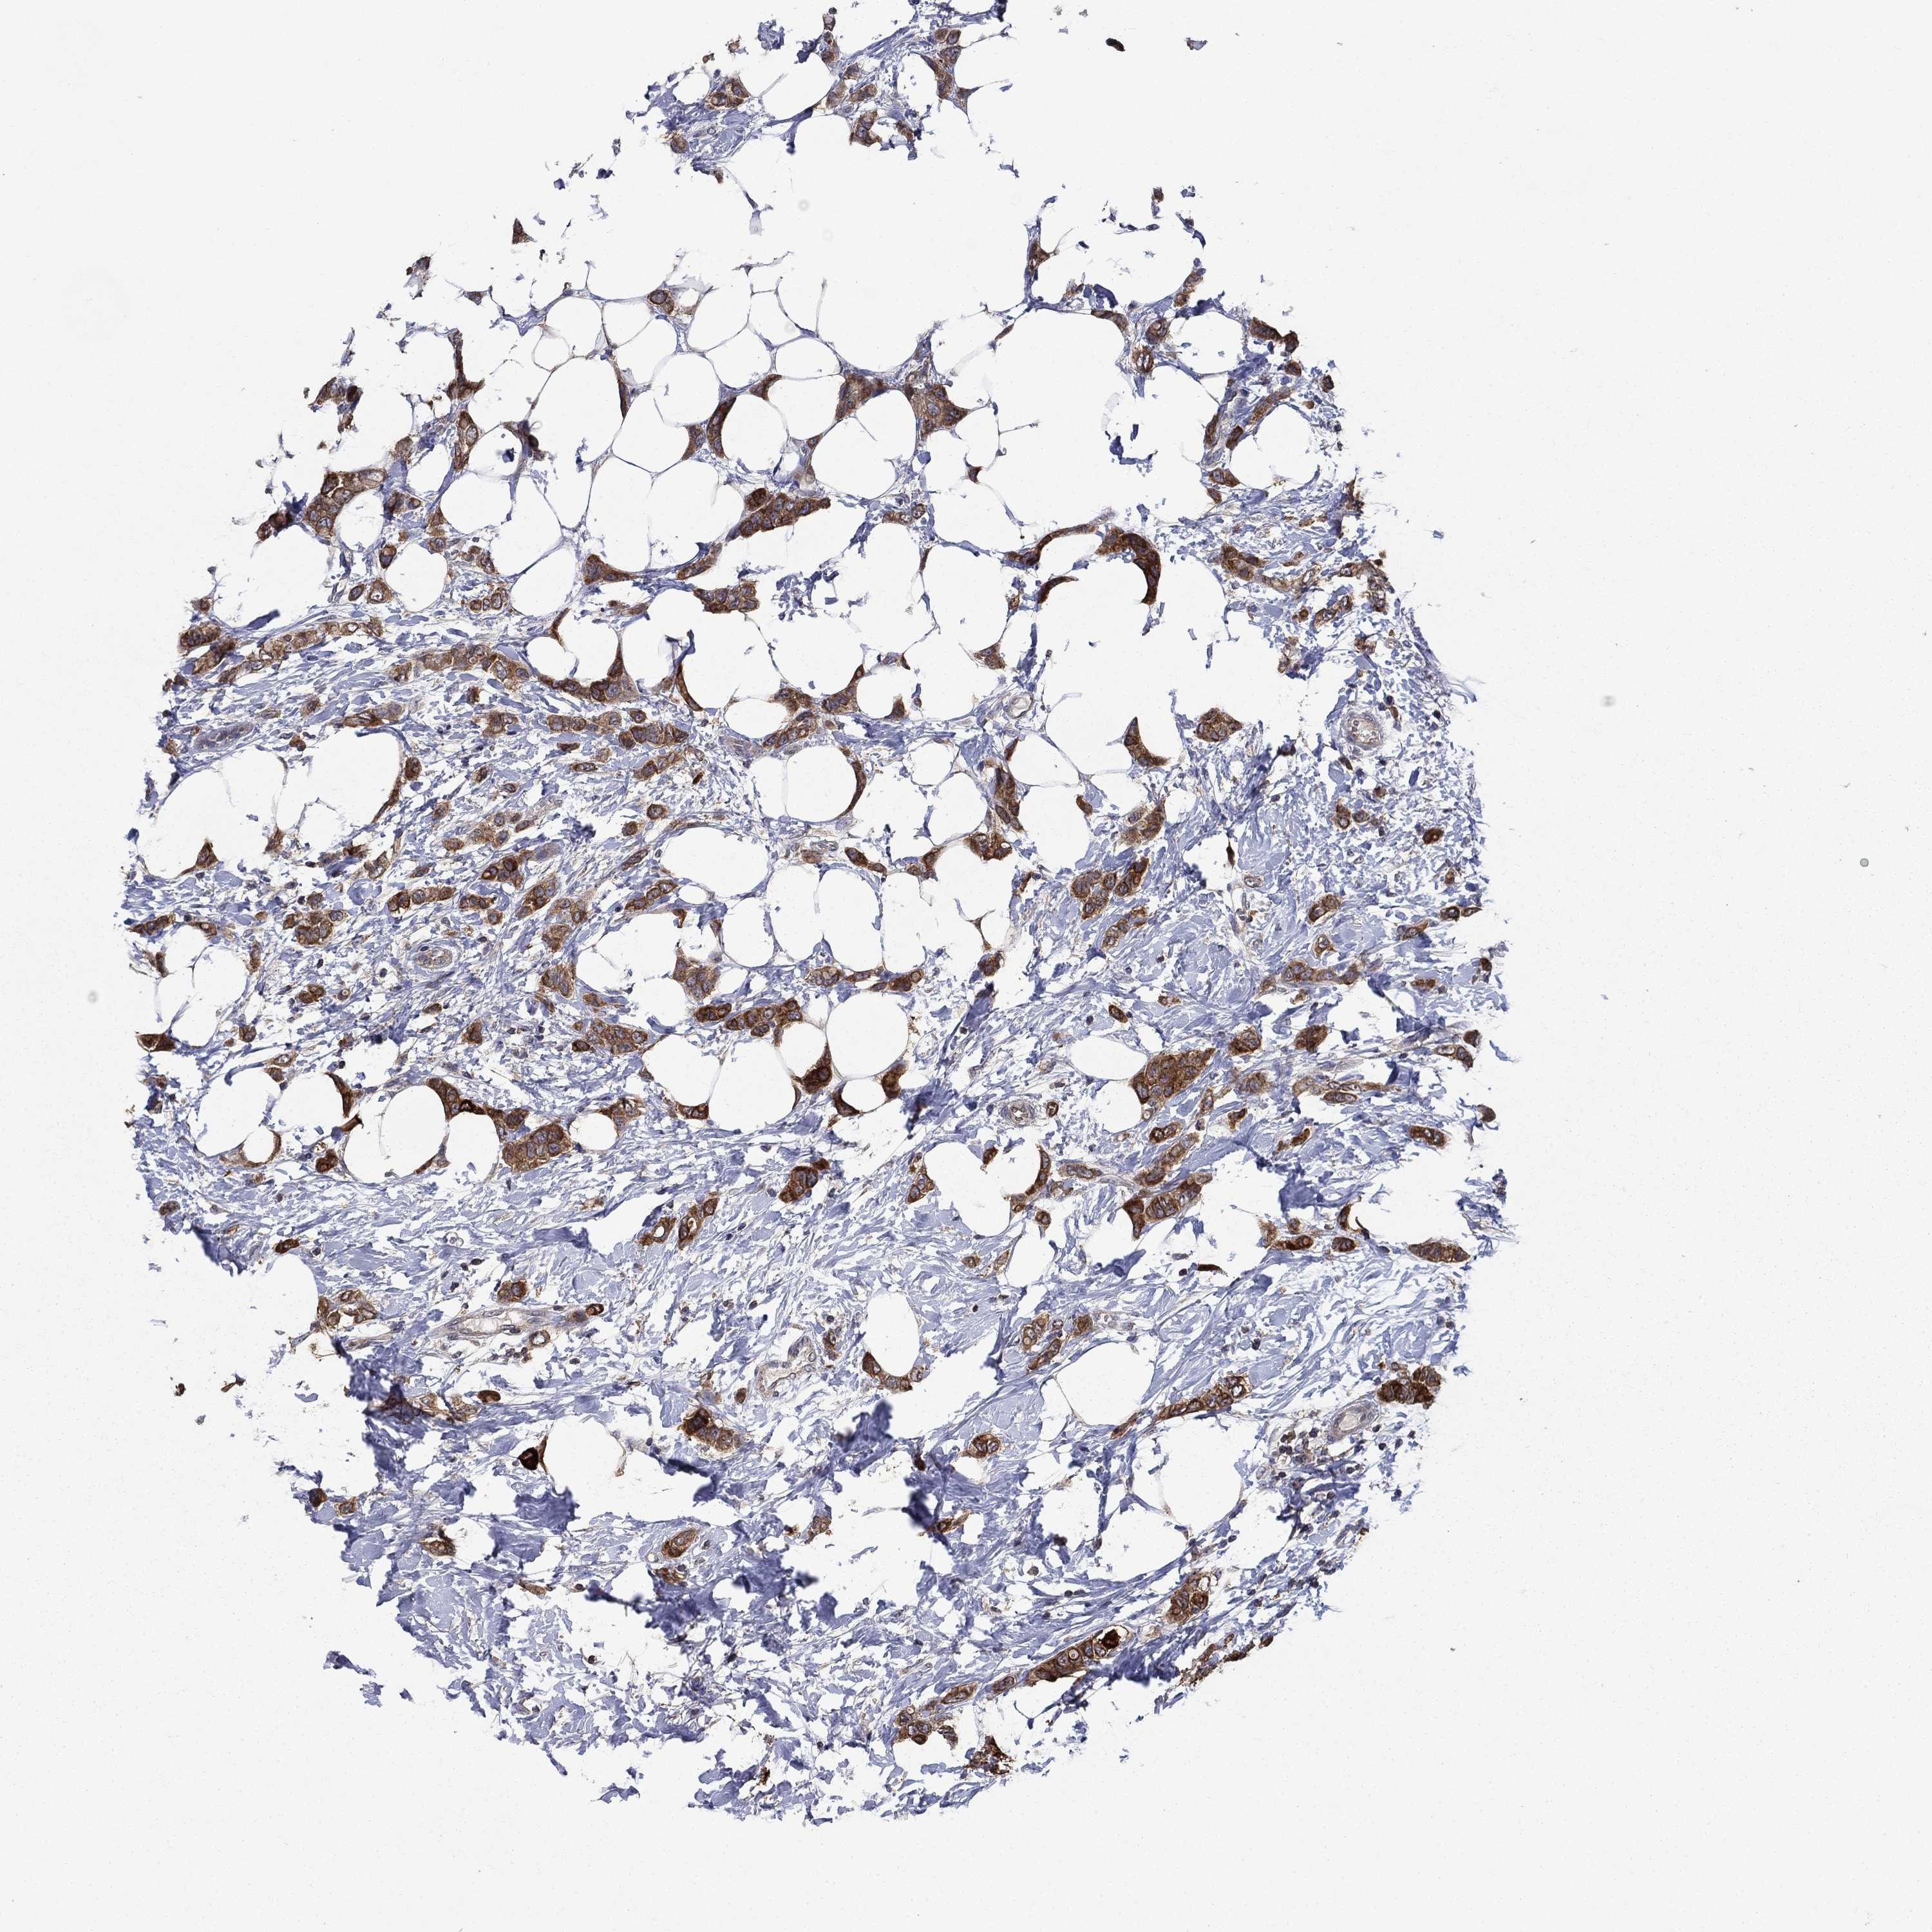

CANCER BREAST CANCER Show tissue menu

BRCA TCGA BRCA VALIDATION PROTEIN EXPRESSION